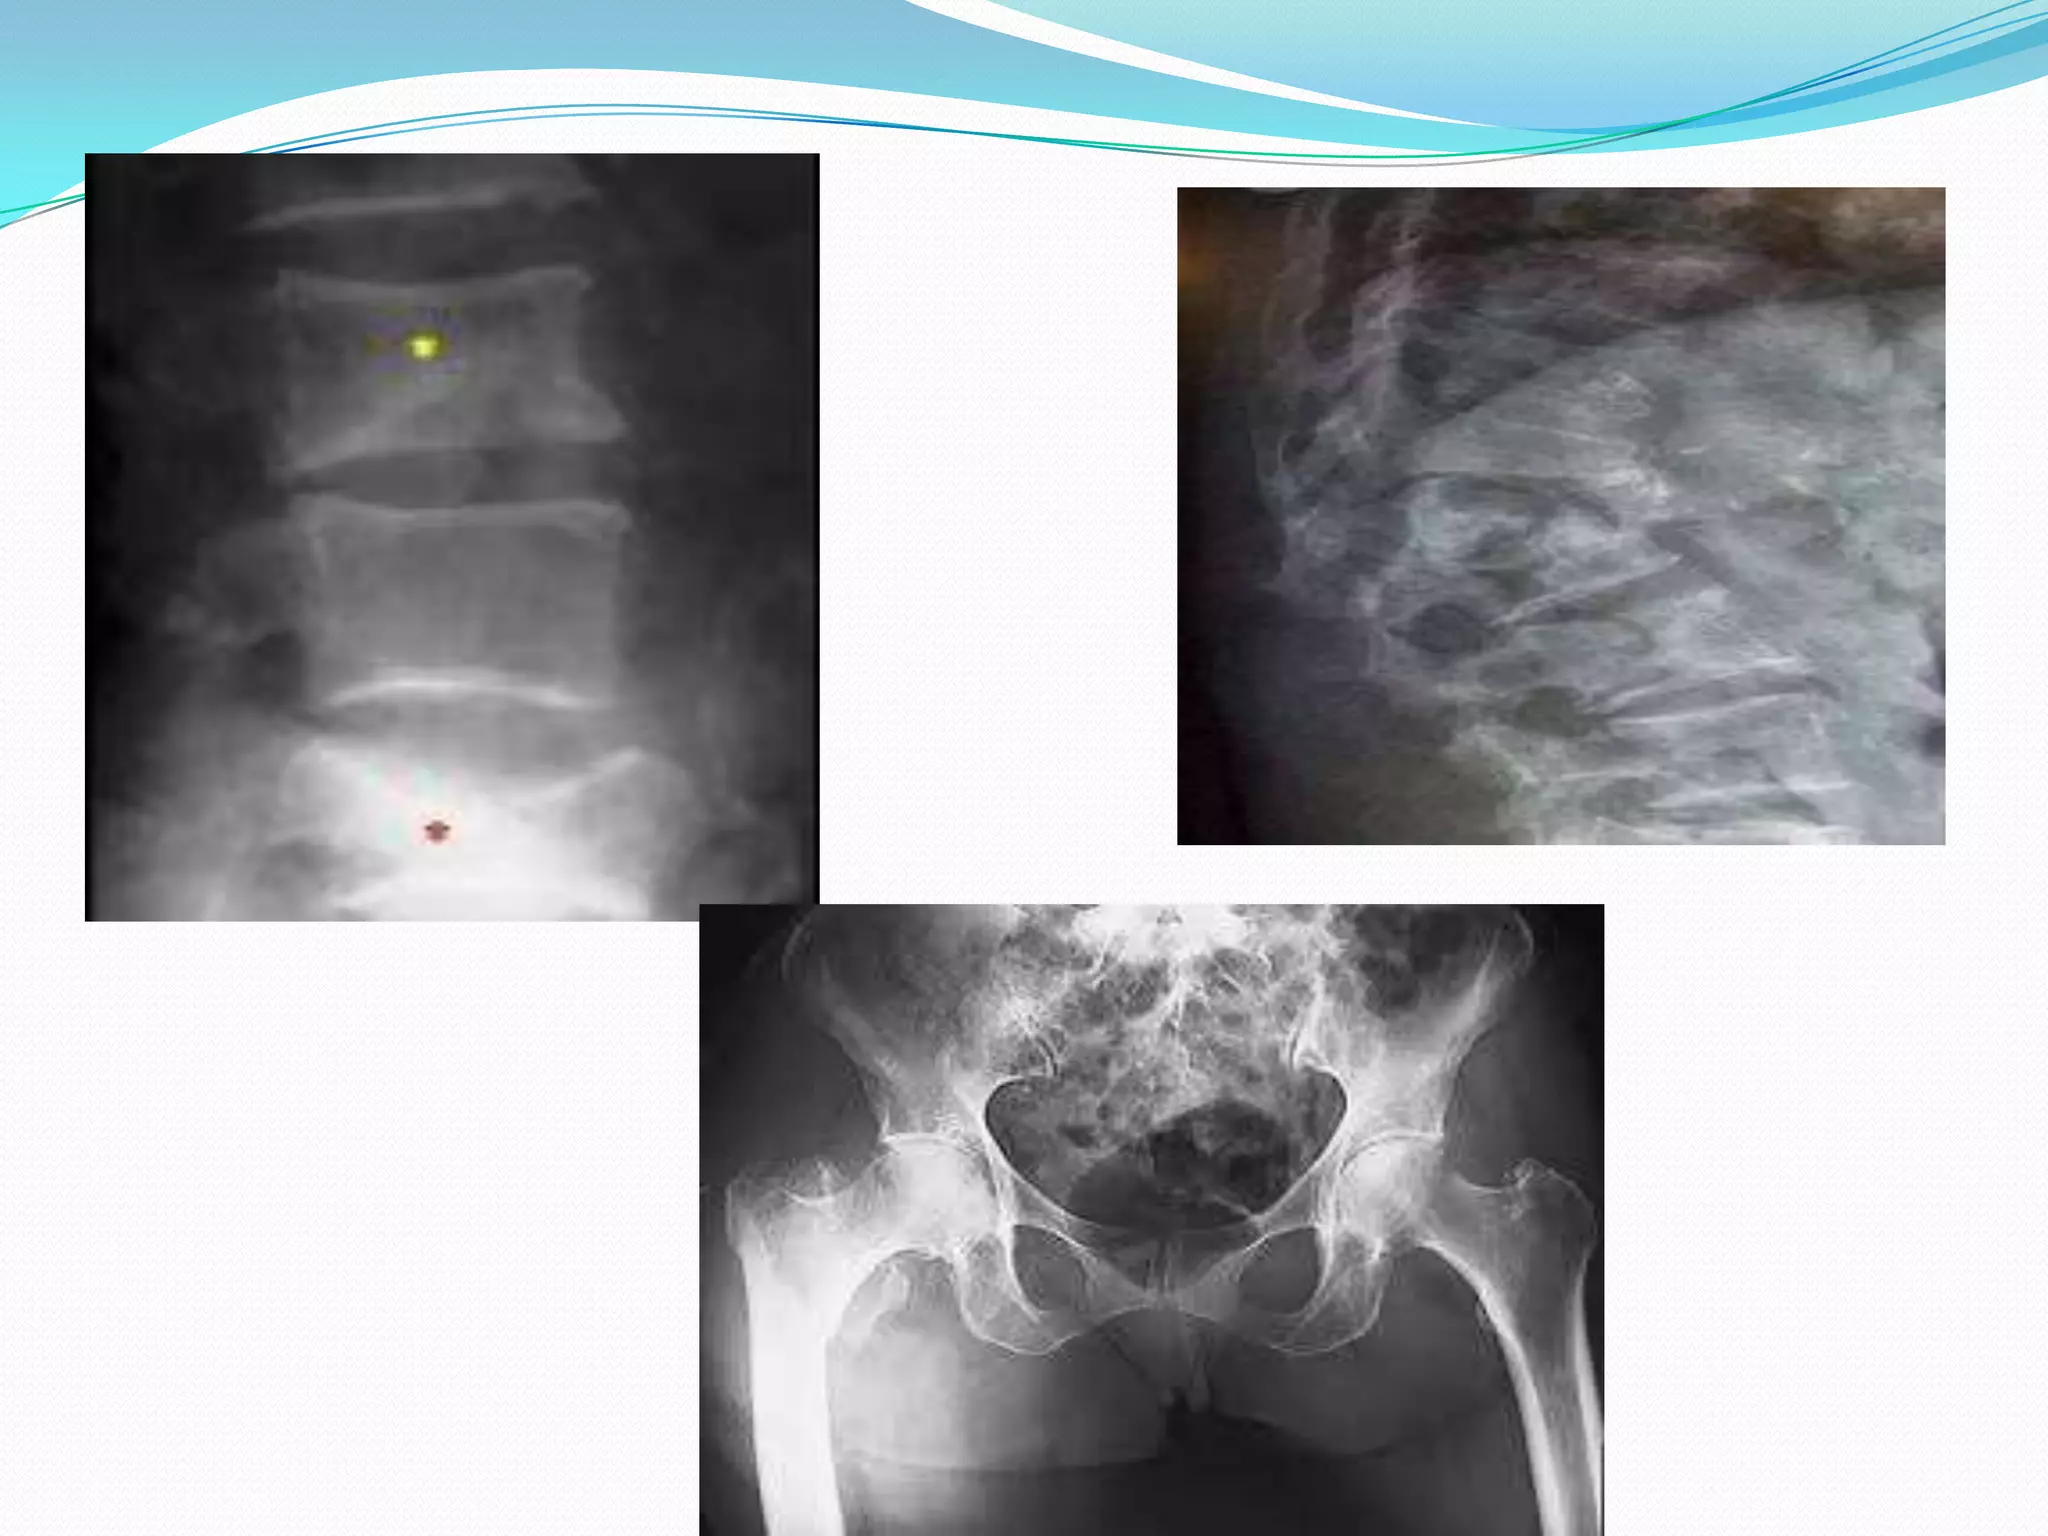

Imaging Studies

 First, obtain plain radiographs if a decrease in bone

mineral density is suspected

 Osteopenia may be apparent as radiographic lucency

but is not always noticeable until 30% of bone mineral

is lost

 Plain radiography is not as accurate as BMD testing

SITES

•Clinically most valuable sampling

–PA Lumbar spine (compression

fracture)

–Proximal femur (hip fracture)

•Use total regions of spine and hip

•Use lowest T-score of these two

•In elderly patient, due to

deformity and degenerative

changes, difficult to interpret

spine scan; then consider hip or

forearm